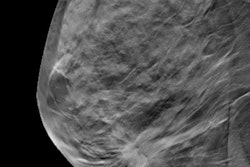

Digital breast tomosynthesis (DBT) is comparable to full-field digital mammography (FFDM) for identifying benign breast lesions, according to a new study published online January 23 in the American Journal of Roentgenology.

DBT has rapidly entered the clinical mainstream, in part because it appears to improve the harm-to-benefit ratio of breast cancer screening by reducing recall rates and finding more invasive cancers than 2D mammography. But DBT's performance in detecting and diagnosing specific benign and malignant lesions compared with FFDM has been unclear, according to Fujii and colleagues.